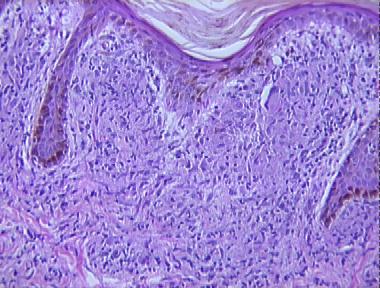

dimorphous leprosy

Histologic Features